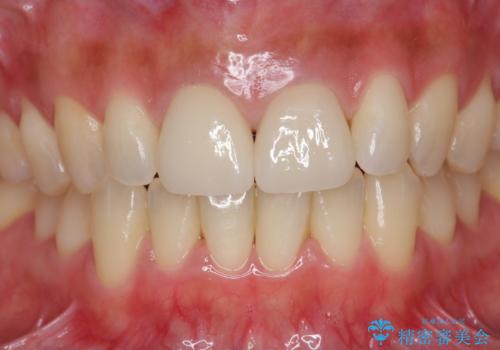

- 32万円(仮歯・ファイバーコア・ジルコニアクラウンスペシャル×2)費用は治療当時の料金となります

ただ見えるクラウンを白くきれいにするのではなく、長期的な歯の予後を考えると根管治療・ファイバーコア築盛・精密な歯牙形成等クリアすべき条件は多々あると言えます。